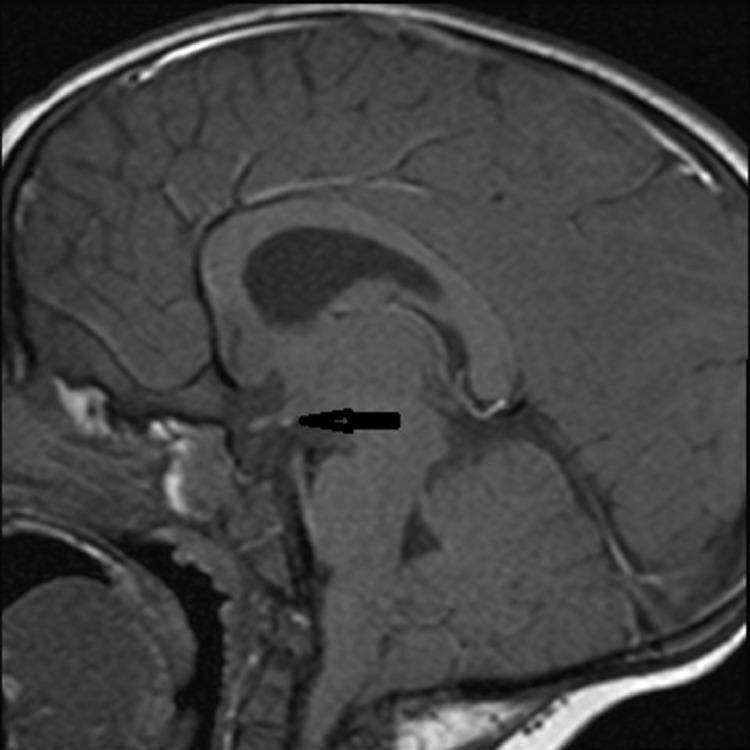

一名男孩的异位神经垂体:病例报告及文献复习

Ectopic neurohypophisis in a boy: A case report and review.

Ectopic neurohypophysis is rare anomaly which is characterized by ectopic location of posterior pituitary lobe (neurohypophysis), pituitary stalk abnormalities and association with dysfunction of anterior lobe related with growth hormone or with multiple dysfunction of the same.We present a rare case of posterior ectopic pituitary and pituitary stalk hypoplasia isolated in 2 year-old male patient.

摘要

异位神经垂体是一种罕见的异常情况,其特征为垂体后叶(神经垂体)异位、垂体柄异常,并伴有与生长激素相关的前叶功能障碍或多种功能障碍。我们报告了一例罕见的2岁男性患者孤立性垂体后叶异位和垂体柄发育不全的病例。